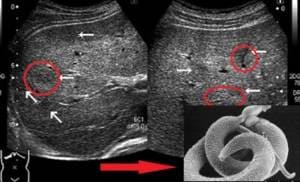

Corrispondente: "Cosa intende dire?" Ramón Nieto: Esattamente quello che sto dicendo anche. Quando ho avuto i primi sintomi di un'infezione parassitaria, non sapevo nemmeno cosa fosse. Non tutti sanno che quando i papillomi iniziano a comparire sulla pelle, ti stanchi rapidamente e dalla tua bocca esce un odore sgradevole, il che significa che i parassiti si moltiplicano all'interno del corpo. Tuttavia, sono andato dal medico e la diagnosi era corretta e si e confermata. Dalla seconda volta, tuttavia, la prima volta mi sono stati prescritti molti sedativi, alcune costose creme per il papilloma e altri peeling. Dalla seconda volta, tuttavia, la prima volta mi sono stati prescritti molti sedativi, alcune costose creme per il papilloma e altri peeling. Sono molto sorpreso durante un viaggio da un parassitologo, che difficilmente riuscivo a trovare. Ha cancellato i vecchi farmaci, ne ha prescritti molti nuovi, ha detto che avrebbe dovuto aiutare. Solo allora mi sono reso conto che, calcolando l'importo che poteva essere prelevato da me, i medici volevano piuttosto aggravare la situazione e il decorso della malattia. Per due mesi tutto è tornato in stato normale. Sì, c'era una stanchezza terribile, ogni tanto apparivano nuovi papillomi, di tanto in tanto qualcosa faceva male, ma niente di critico per la mia salute. Poi, improvvisamente, sono comparsi dolori acuti nella zona dei reni. Letteralmente in un colpo solo. La sera, quando sono andato a letto, tutto andava ancora bene. E la mattina riuscivo a malapena ad alzarmi dal letto, era di nuovo male. Sono rivolta subito dai dottori. Corrispondente: "E cosa hanno detto?" Ramón Nieto: Era ovvio che fosse in preda al panico. Dissero che erano larve parassitarie che avevano mangiato vivo il mio rene destro. Ci è stata offerta una scelta: o aprire lo stomaco e pulire tutto, oppure sottoporsi a cure conservative in ospedale. Altrimenti, il rene si rinuncia alle sue funzionalita e le larve si diffondono in tutto il corpo e riempiano gli organi interni vicini. Garantito che mi ucciderà. Un'operazione del genere alla mia età è estremamente pericolosa, quindi l'unica opzione era l'ospedale. Non dirò quale fosse il prezzo, ma era sopra ogni limite possibile e ragionevole. E, naturalmente, fuori della possibilita del mio portafoglio. Ufficialmente, la procedura è stata eseguita per pochi centesimi. Da un lato, ora capisco che è stato tutto un "divorzio" per denaro, con una posta in gioco sulla mia vita. Ma quando rischi di morire, la logica scende al secondo piano. Ho accettato l'importo proposto, ho trascorso tre settimane in ospedale come ricoverato, poi ci sono andato tutti i giorni per controllo. Durante il trattamento, il dolore prima si è indebolito e poi è sembrato scomparire completamente. Corrispondente: "Quindi hanno aiutato?" Ramón Nieto: Oltre al fatto che tutto questo si poteva evitare, e in modo molto semplice, hanno aiutato. Anche se, dal loro punto di vista, hanno appena vinto un altro paziente. Inoltre, l'aiuto è stato solo locale, colpendo con successo solo una colonia di parassiti. C'erano tre specie in totale, cioè almeno tre nidi di questo abominio dentro di me. Inoltre, la situazione si è sviluppata terribilmente. Il cuore mi faceva male, la pressione mi faceva impazzire, anche se questo non era mai successo prima, la testa mi faceva un male terribile, le gambe iniziarono a gonfiarsi. A volte non riuscivo ad alzarmi dal letto per tutto il giorno. Allo stesso tempo, guardavo costantemente i dottori, spendevo regolarmente molti soldi in medicine costose, mi riempivo i pugni di pillole. E mi sentivo spezzato di piu ogni giorno. In effetti, a un certo punto ho pensato che sarei morto così. Non c'è stato il minimo miglioramento delle funzionamento del organismo. Corrispondente: "Ma lei è seduto qui davanti a me. Com'è andata?" Ramón Nieto: Il caso ci ha aiutato. È venuto da lui un vecchio amico. Ha visto le mie condizioni, ha cominciato a interessarsi. È stato sciocco negarlo, l'ho detto così com'è. Mi ha salvato. Piuttosto, all'inizio cadde in uno stato di profonda rabbia e iniziò a imparare i nomi dei dottori. Poi ho fatto un paio di telefonate e lo stesso giorno mi hanno portato un nuovo prodotto antiparassitario. Poi ho avuto paura, stavo per rifiutare, ma non c'era nulla da perdere dall'altra parte e ho deciso di provare. Letteralmente la mattina un giorno dopo, mi sono alzato dal letto per la prima volta entro 15 minuti dal risveglio e non dopo 3-4 ore. E dopo 12-14 giorni, ho notato che il dolore ha cominciato a diminuire. Anche i sintomi delle complicanze iniziarono a diminuire. Come mi hanno spiegato i medici, già consigliati dal mio amico, il farmaco ha distrutto i parassiti e bloccato la loro capacità di riprodursi. Non hai idea di cosa mi sia successo nei primi giorni dopo aver iniziato a prendere il prodotto. Sembra più un film dell'orrore. In ogni caso, dopo 3 mesi sono tornato in uno stato di salute. Considerando quanto fosse grave la mia salute, è un miracolo che abbia purificato il mio corpo e mi abbia guarito in così breve tempo. Corrispondente: "Quindi siete riusciti a ripulire il corpo da tutti i tipi di parassiti? E cosa è successo ai medici che lo hanno "curato" per primi?". Ramón Nieto: Questo può sembrare sorprendente, soprattutto date le mie condizioni, ma sì, ho ripulito completamente il mio corpo dai parassiti e sono guarito. La diagnostica all'inizio del trattamento ha mostrato che i parassiti ostruivano letteralmente l'intestino, vivevano nei vasi, i prodotti della loro attività vitale entravano nel flusso sanguigno, provocando infiammazioni e distruggendo gradualmente le parti del cuore. In generale, l'intero corpo era pieno di vermi di vario genere. E a quanto pare li ho infettati molto tempo fa, solo un fattore è servito da impulso per la riproduzione attiva dei parassiti, che mi ha quasi ucciso. Secondo i medici già normali che mi hanno osservato dopo che ho lasciato quegli assassini in vestaglia bianca, almeno due abitanti su tre del Paese sono infetti da parassiti. Per quanto riguarda i medici che mi hanno iniettato denaro, sono stati arrestati e stanno testimoniando. Si è scoperto che esiste un folto gruppo di operatori sanitari di diverse istituzioni a beneficio delle persone. Ecco perché voglio avvertire tutte le persone di fare attenzione. Se hanno fatto questo a una persona abbastanza famosa, ho paura di pensare a cosa stanno facendo a coloro che sono impotenti contro questi medici bastardi. In generale, tutti possono fare una diagnosi indipendente. Con la crescita di papillomi, alitosi, frequenti mal di testa ed emicranie, affaticamento, difficoltà ad alzarsi al mattino, il 90% è infetto da parassiti. Mi sono anche reso conto che la metà di tutte le malattie gravi sono causate da parassiti. Infarti, ictus, tumori, sepsi, diabete, ipertensione, artrite, artrosi: quasi tutte le malattie possono essere causate dalla presenza di vermi o amebe nel corpo umano. Ho quasi avuto l'insufficienza renale e malattia coronarica. E ha subito almeno 5-6 microictus a causa del passaggio di tossine parassitarie attraverso il cuore. Corrispondente: “Può dirci di più sul prodotto con cui è stato trattato?” Ramón Nieto: Senza dubbio. Stiamo parlando di Nemanex, un nuovo prodotto sviluppato congiuntamente in Svizzera. Attualmente è disponibile solo nei paesi in via di sviluppo, poiché i volumi di produzione sono piccoli e insufficienti anche per soddisfare la richiesta di ordini di prodotti in questi paesi.